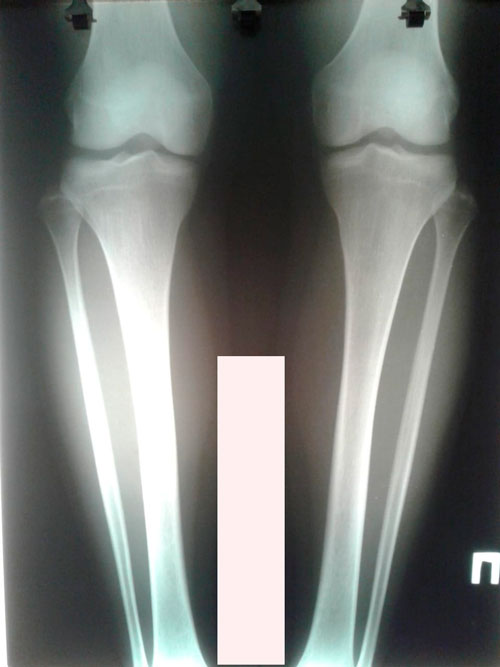

Исходник - 28 лет. Шымкент.

Дата операции - 05.03.2019г.

Дата снятия аппаратов - 26.06.2019г.

Срок сращения - 110 дней.